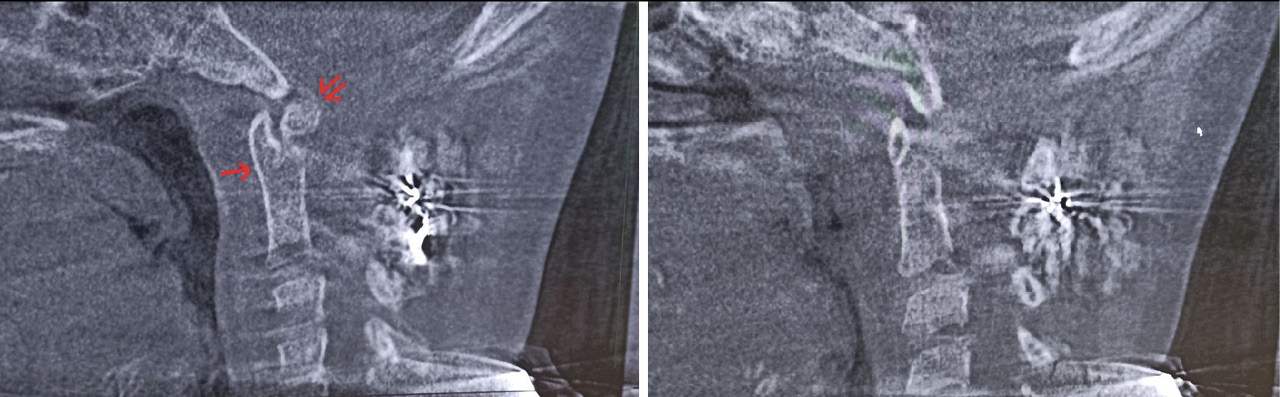

Пациентка Е. 9 лет обратилась на прием с жалобами на ограничение поворотов головой. Со слов матери, в мае 2018 г. ребенку проводилось оперативное лечение по поводу травмы шейного отдела позвоночника. Медицинские заключения не были предоставлены. При осмотре ребенок с синдромом Дауна. Голова по средней линии, пальпация области шейного отдела позвоночника безболезненна, объем пассивных и активных наклонов головы соответствовал нормативным значениям. При этом амплитуда пассивных и активных ротационных движений в шейном отделе позвоночника составила 15° и 20º в каждую сторону соответственно. При последующем ортопедическом осмотре было выявлено нарушение осанки по типу «сутулая спина» по Штаффелю. По данным анализа представленного диска с результатами ранее проведенной мультиспиральной компьютерной томографии шейного отдела позвоночника (дата исследования – май 2018 г.) был выявлен перелом зубовидного отростка С2 позвонка типа 1 по классификации L. D. Anderson и R.T. D'Alonzo, со смещением верхушки зубовидного отростка кпереди [9]. Плоскость перелома зубовидного отростка аксиса косая, края отломков неровные, нечеткие, диастаз между отломками неравномерный (рис. 5).

Рис. 5. Компьютерная томография шейного отдела позвоночника, сагиттальный срез (А), фронтальный срез на уровне зубовидного отростка С2 позвонка (Б). Стрелкой обозначено место перелома зубовидного отростка С2 позвонка

Для оценки ситуации в динамике была проведена КЛКТ, на которой на фоне динамической нерезкости (ребенок был неусидчив) и артефактов от металлоконструкции было отмечено следующее: суставные рентгеновские щели в латеральных атлантоаксиальных суставах: справа – не прослеживается, слева – неравномерно сужена до 0,4 мм в наиболее узком месте (рис. 6). Рентгеновская щель срединного атлантоаксиального сустава в сагиттальной плоскости не прослеживается (рис. 7А), в парасагиттальной плоскости – прослеживается, неравномерная (рис. 7Б). Зубовидный отросток С2 позвонка визуализируется в виде 2 фрагментов, дистальный из которых вместе с передней дужкой С1 позвонка представлен в виде не полностью слитного костного образования. Проксимальный фрагмент, лоцирующийся в проекции верхушки зубовидного отростка С2 позвонка, представлен в виде свободно лежащего отломка с неравномерно склерозированным контуром в проекции диастаза (см. рис. 7). Данная рентгенологическая картина соответствует состоянию после оперативного лечения по поводу травмы шейного отдела позвоночника со стабилизацией металлоостеосинтезом С1–С2 позвонков. Неправильно сросшийся перелом зубовидного отростка С2 позвонка. Частичный анкилоз срединного атлантоаксиального сустава и полный анкилоз правого латерального атлантоаксиального сустава.

Рис. 6. Конусно-лучевая компьютерная томография краниовертебральной области, фронтальный срез на уровне зубовидного отростка С2 позвонка